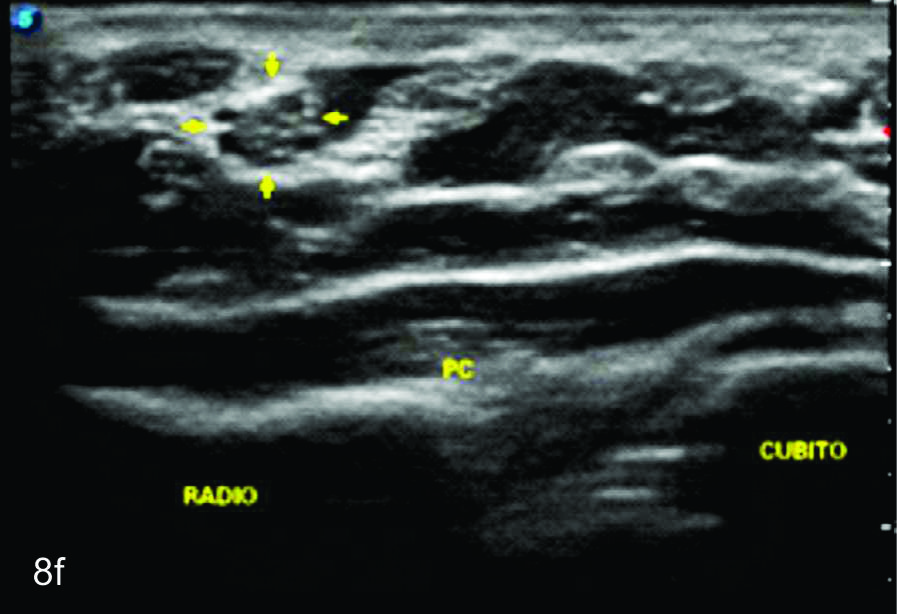

Figura 8

Nervio mediano

Serie de cortes axiales del nervio mediano desde su origen a nivel del hueco axilar hasta el sector distal del antebrazo previo a su ingreso al túnel del carpo. Se identifica el mismo señalado por flechas amarillas y con la palabra mediano. AA-arteria axilar, VA- vena axilar, AH- arteria humeral, VH- vena humeral, VB- vena basilar, AC- ateria cubital, VC- vena cubital, BA- músculo braquial anterior, PR- músculo pronador cuadrado, FS- músculo flexos superficial, FP- músculo flexor profundo, PC- músculo pronador cuadrado. A- axila, se identifica el nervio superfical a la arteria axilar, B- tercio medio del brazo en canal bicipital medial, lateral a la arteria humeral, C- codo, medial al tendón distal del bíceps braquial y a la arteria humeral luego de cruzarla, superficial al músculo braquial anterior, D-antebrazo sector cefálico, entre las dos cabezas del pronador redondo, E- tercio medio del antebrazo, entre los músculos flexor superficial y profundo F- tercio distal antebrazo, superficial al pronador cuadrado.

Figura 14 e, f, g y h

Lesión traumática del plexo braquial luego de accidente en moto.

EyF-Cortes comparativos a nivel de cara anterior de brazo derecho o afectado (E) y brazo izquierdo o sano (F), en donde se identifica la clara asimetría en el volumen y ecogenicidad de los planos musculares (flechas azules) en relación a cambios por atrofia. H- diáfisis humeral. GyH- Cortes comparativos a nivel de la cara anterior del antebrazo derecho o afectado (H) e izquierdo o sano (G), demuestra hallazgos similares. R- Diafisis radio, C- Diafisis cubito.